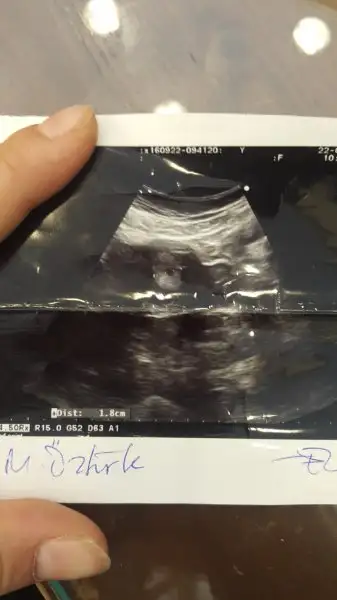

Ona benziyor? Doktora sormadinizmiBu bebek mi????